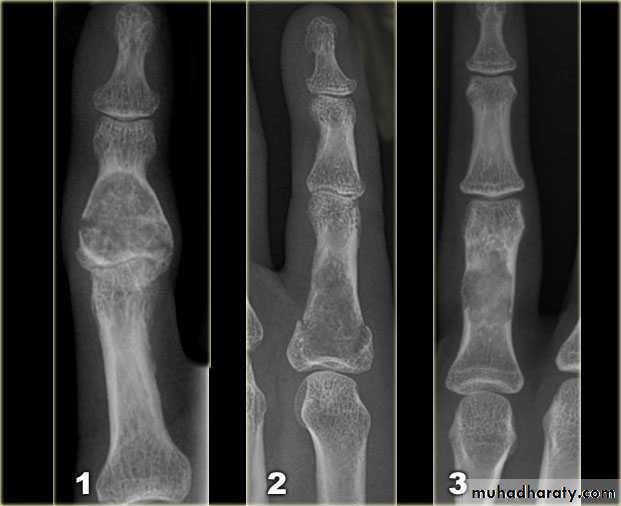

1.Zone of transition

2.The adjacent cortex

3.Expansion

the initial radiological decision is usually to try &decide whether the solitary lesion is benign or its aggressive by looking for the following features on plain radiographs & CT :